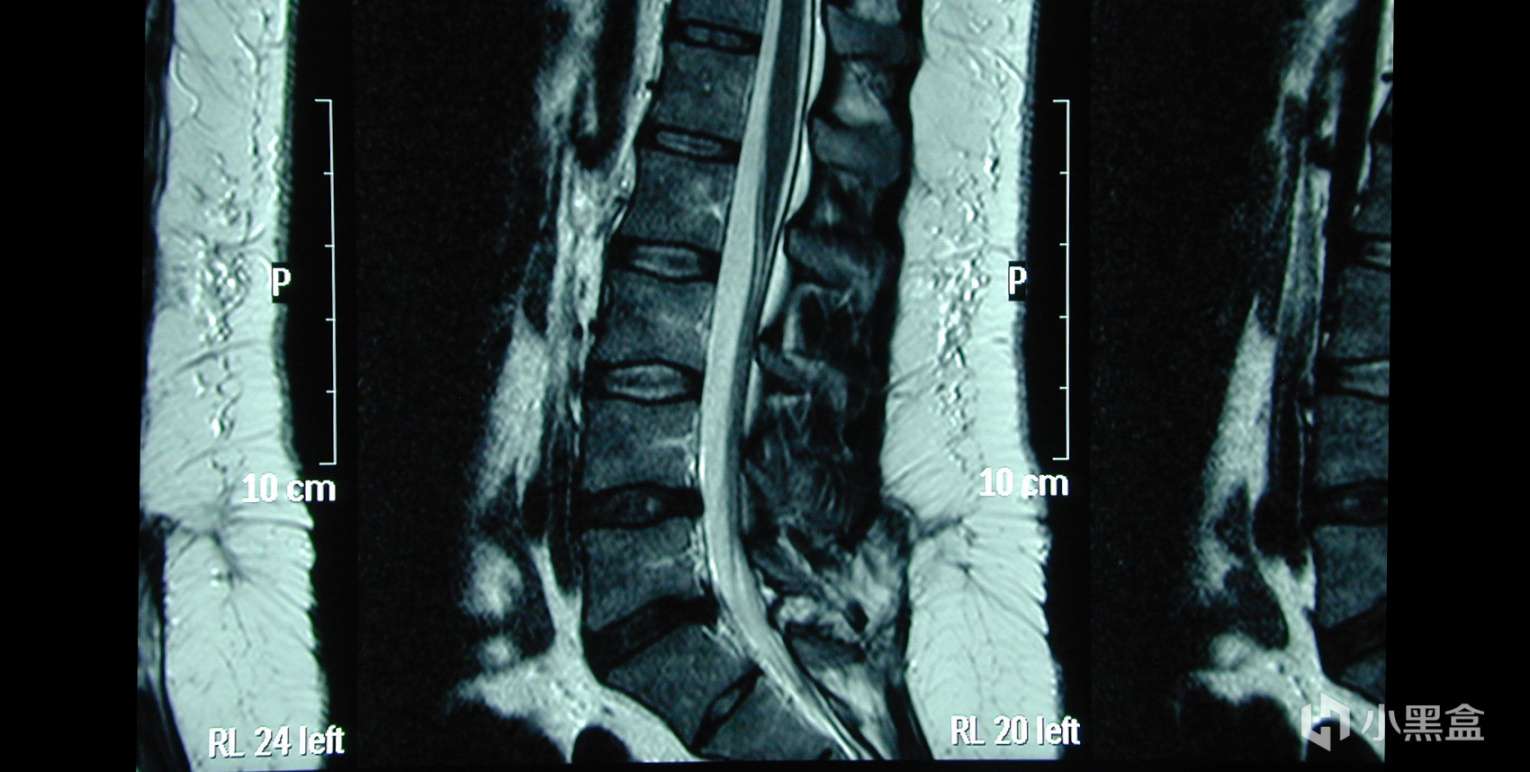

時間到了2023年,目前註冊了ChatGPT賬號,將這些內容輸入給GPT大模型,GPT告訴她亞歷克斯患有脊髓栓系綜合症,隨後母親帶他去醫院做了核磁共振,並告訴醫生亞歷克斯可能患有脊髓栓系綜合症(TCS)。

脛骨診斷後,醫生說這是一種非常罕見的先天缺陷,亞歷克斯患有的是隱式的脊髓栓系綜合徵,即部分脊髓未完全發育,部分脊髓和神經暴露,由於是隱式所以背部裂口並不明顯,很容易被忽略,最終ChatGPT也成功幫助亞歷克斯找出病因,拯救了這名年輕的男孩!